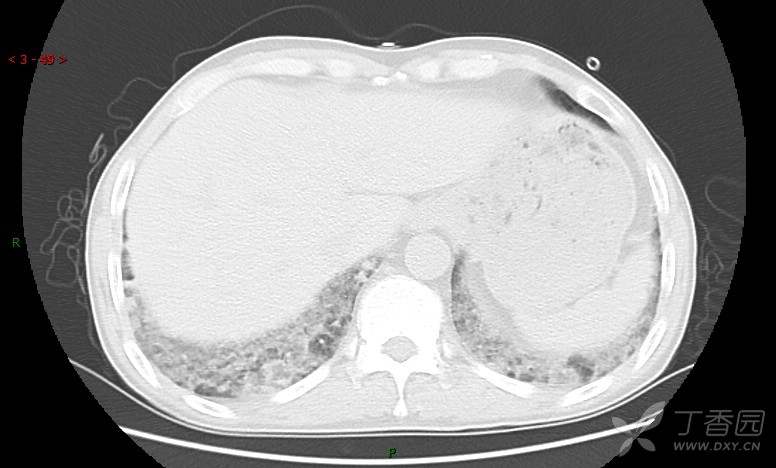

患者男,42岁,咳嗽半年余,加重伴憋喘2月余。

患者半年余前无明显诱因出现间断咳嗽,干咳为主,偶咳少量黄白痰,剧烈咳嗽或运动后可出现轻度憋喘,无高热、脓臭痰,无胸痛、咯血及晕厥,无低热乏力及盗汗,无心前区压榨感及夜间阵发性呼吸困难,初未在意,未予正规诊治。2月余前患者自觉上述症状较前加重,咳嗽、憋喘明显,黄白色粘痰略有增多,伴有发热,热前伴有畏寒、寒战,体温最高达38.9℃,先后就诊多家医院,入住重症监护室,未行气管插管,考虑“重症肺炎”,给予“美罗培南、复方磺胺甲噁唑”等药物抗感染,“卡泊芬净”抗真菌,并给予“甲泼尼龙”等药物治疗35天,经治疗后症状好转于2018-04-02出院。患者自出院后仅应用中药治疗(具体不详),并给予家庭氧疗,平素仍有间断咳嗽,咳少量黄白色粘痰,活动后憋喘明显,活动耐量差,以卧床为主。